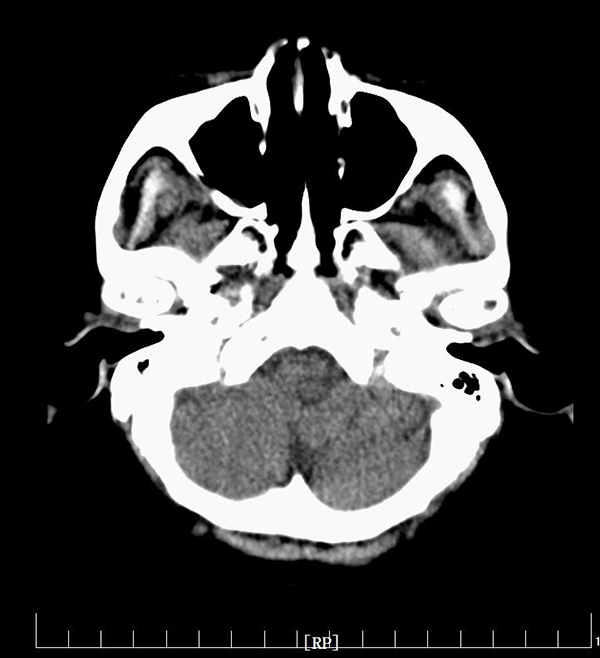

近日,陕西省核工业二一五医院神经内科一病区王建峰主任脑血管病团队借助CT应用领域前沿科技——头颅CT灌注成像(CTP)技术,为一例高龄醒后卒中患者成功进行了颅内动脉取栓术,这标志着二一五医院神经介入技术再上新高度。...